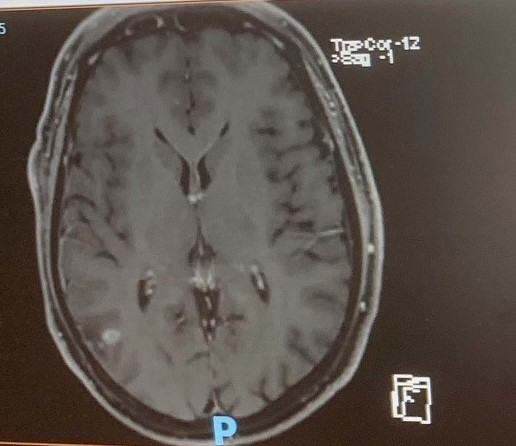

The results from the MR-scan were very positive. There are no signs of tumour activity in or around the operation site. Similarly, there are no signs of tumour activity anywhere else within my brain. Just for interest, I have included two images from the MR-scan. The left-hand image was recorded in September and shows the tumour as a fuzzy white disc in the bottom left section of the picture. The same area in the right-hand image shows that the hole left after the operation is filled with cerebral fluid. No fuzzy white discs can be seen, so for the time being things are looking good.